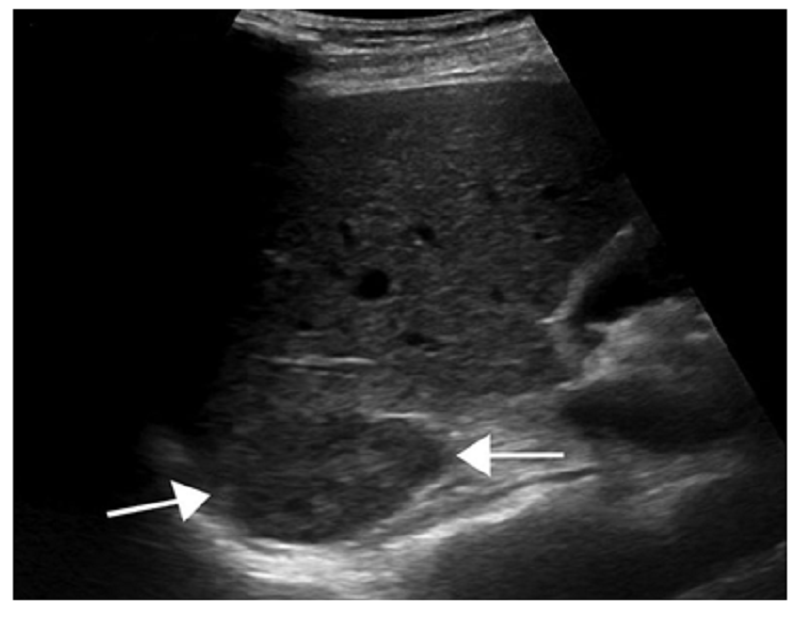

Khi siêu âm sẽ thấy được sự hình thành các echogenic đơn lẻ, tín hiệu âm thanh đi qua máu trong xoang hang sẽ có sự khuếch đại.